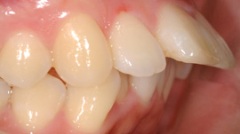

審美的治療の実例

出っ 歯が気になって来院した患者様です。海外に行くことが決まっていたので、矯正治療をするだけの時間の余裕がありませんでした。そこで、上の前歯4本をオー ルセラミッククラウンに変えました。いかがですか?どれが人口の歯か見分けがつきません。患者様ご本人も大満足してくださいました。

当院では咬み合わせ、歯列のみならず、歯肉との調和も考慮し治療にあたります。自然さを追求し、治療した後も結果を長く安定させるように、しっかりとメインテナンスサポート致します。